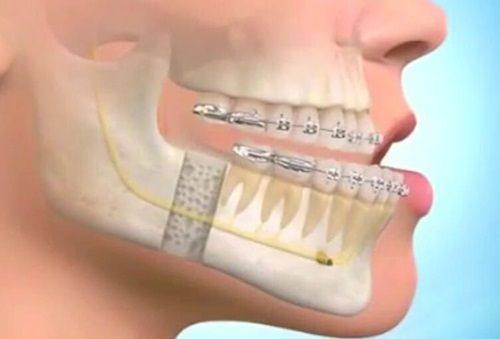

牙齿畸形矫正:杨四维医生专注各类牙齿畸形矫正项目,能够根据患者的口腔基础条件定制个性化矫正方案,兼顾口腔功能修复与面部美观提升,帮助患者改善牙齿排列问题,优化口腔健康状态与整体魅力。